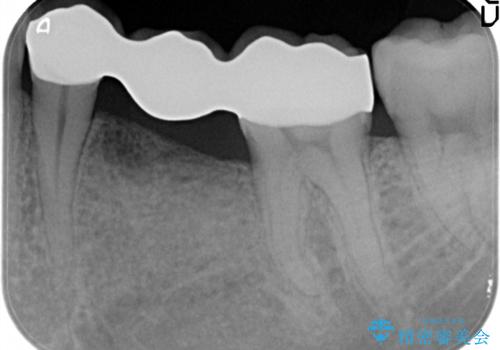

奥歯が痛い。乳歯を抜歯し、ブリッジによる咬合回復。

- 晩期残存した乳歯が痛くなったことを主訴に来院されました。

歯周病が進行していたため、抜歯を行い咬合回復を行いました。

インプラントは希望されなかったため、ブリッジにて治療を行っております。

欠損補綴に対し、インプラントは有効な手段ですが比較的高額で、手術を伴います。

患者様によってはブリッジを選択される方もいらっしゃいます。